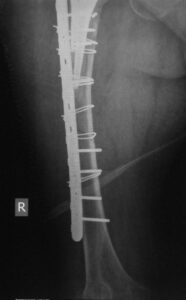

- Περιπροθετικό κάταγμα στην περιοχή στο πέρας του εμφυτεύματος ισχίου σε θήλυ ασθενή .

- Εσωτερική οστεοσύνθεση με πλάκα με αλληλοεπικάλυψη των εμφυτευμάτων για να μην υπάρχουν υψηλές συγκεντρώσεις φορτίων (stress risers)

- H οστεοσύνθεση σε οστεοπορωτικoύς ασθενείς αρχίζει από το γόνατο με σωστή εφαρμογή του εμφυτεύματος και φθάνει μέχρι το ισχίο για να μην υπάρχουν stress risers.

Tα περιπροθετικά κατάγματα σε ηλικιωμένους πρέπει στην οστεοσύνθεση να περιλαμβάνουν ολόκληρο το μήκος του οστού, με αρκετή ελαστικότητα, προάγοντας έτσι την πώρωση και διατηρώντας ταυτόχρονα την σταθερότητα του συστήματος.